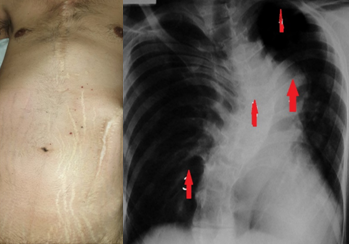

Οισοφαγοστομία. Αποκλεισμός κατώτερου οισοφάγου (Ευγενική παραχώρηση Dr. V. Penopoulos)